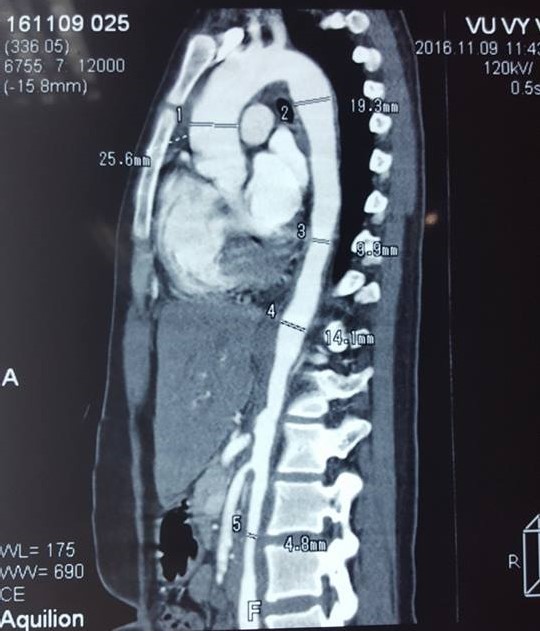

Hình ảnh tổn thương lan tỏa động mạch chủ với rất nhiều chỗ phình và hẹp được ghi nhận. |

Trong trường hợp bệnh nhân V.V.A, do đặc điểm cao huyết áp người trẻ, đau 2 chân khi hay gắng sức, kèm theo âm thổi động mạch thận 2 bên, kết hợp nhiều triệu chứng gợi ý khác nên các bác sĩ đã chủ động chẩn đoán chứng bệnh Takayasu và kết quả là chính xác với hình ảnh tổn thương lan tỏa động mạch chủ và động mạch thận 2 bên trên CTscan mạch máu có thuốc cản quang.